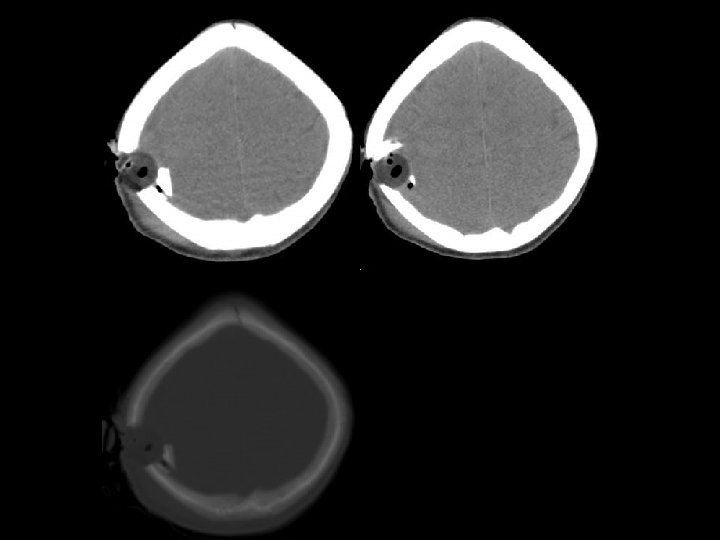

PROTOKOL CT n “RUTIN”: fossa posterior dan regio supratentorial (ketebalan irisan= 5 mm) n “TRAUMA”: fossa posterior (2. 5 mm), regio supratentorial (5 mm) n “TEMPORAL BONE”: <1 mm pada irisan axial atau coronal n “ORBITS/FACIAL BONES”: 1. 25 mm axial/coronal orbits

PENDEKATAN PADA CT OTAK n Lihat pada scout film: adakah fraktur pada n n n upper cervical spine atau skull Lihat adakah asimetri otak Lihat pada sulci, Sylvian fissure dan cisterns untuk menyingkirkan perdarahan subarachnoid Ubah kondisi untuk menilai subdural collection Lihat pada kondisi tulang untuk fraktur Tentukan lesi tersebut intraaxial (di dalam otak) atau extraaxial (di luar otak)